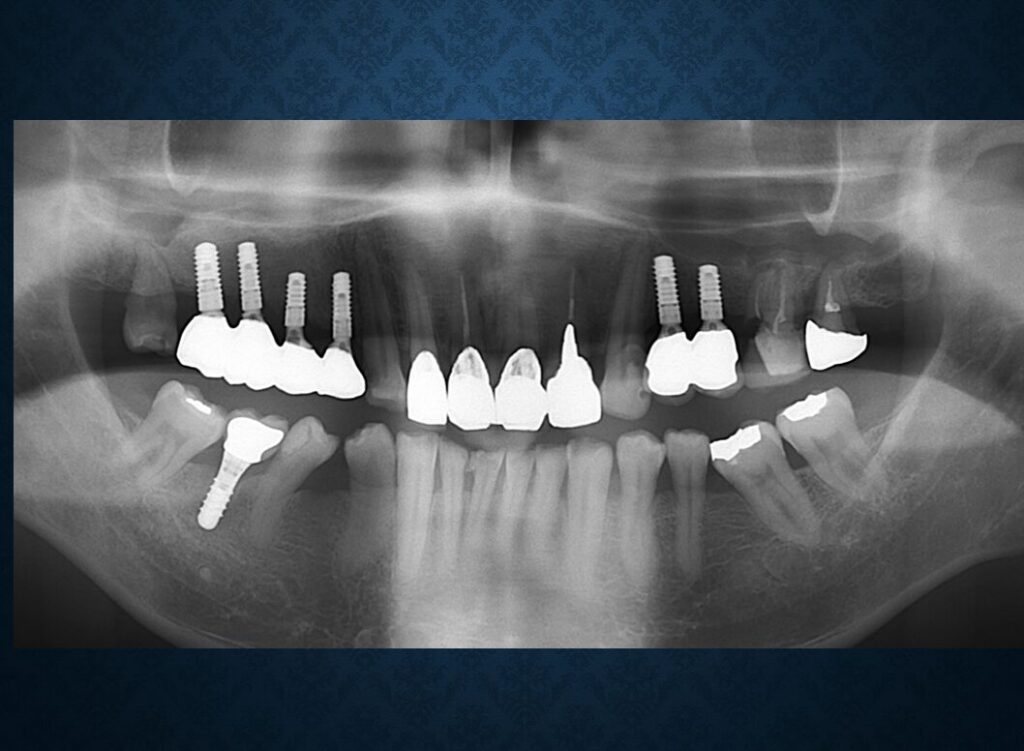

40代フィリピン人男性の方でした。欠損部には入れ歯が入っていました。インプラントに代えて欲しいというご希望でした。職業は会社経営、モデル、英会話教師、ボディービルダー、六本木警察フィリピン語講師、映画俳優など多岐にわたり、日本だけでなく、オーストラリア、台湾、スペインなどを渡り歩いている方でした。多忙を極めていらしたので治療は度々中断しましたが、無事にゴールできました。